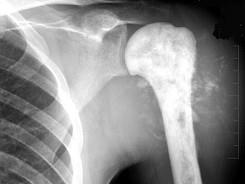

问题 28岁男性患者,右肱骨上段肿痛1个月,疼痛以夜间明显,摄片如图所示,最可能的诊断是 ( )

选项 A、软骨肉瘤 B、骨软骨瘤 C、成骨性骨肉瘤 D、皮质旁骨肉瘤 E、溶骨性骨肉瘤

答案 C